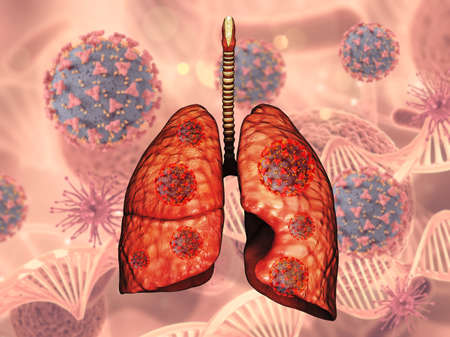

A detailed 3D representation of human lungs, showing the effects of respiratory diseases like cancer, asthma, and bronchitis on a red and blue medical background

A digital illustration of human lungs, depicted in red, surrounded by virus-like particles, symbolizing respiratory health and infection.